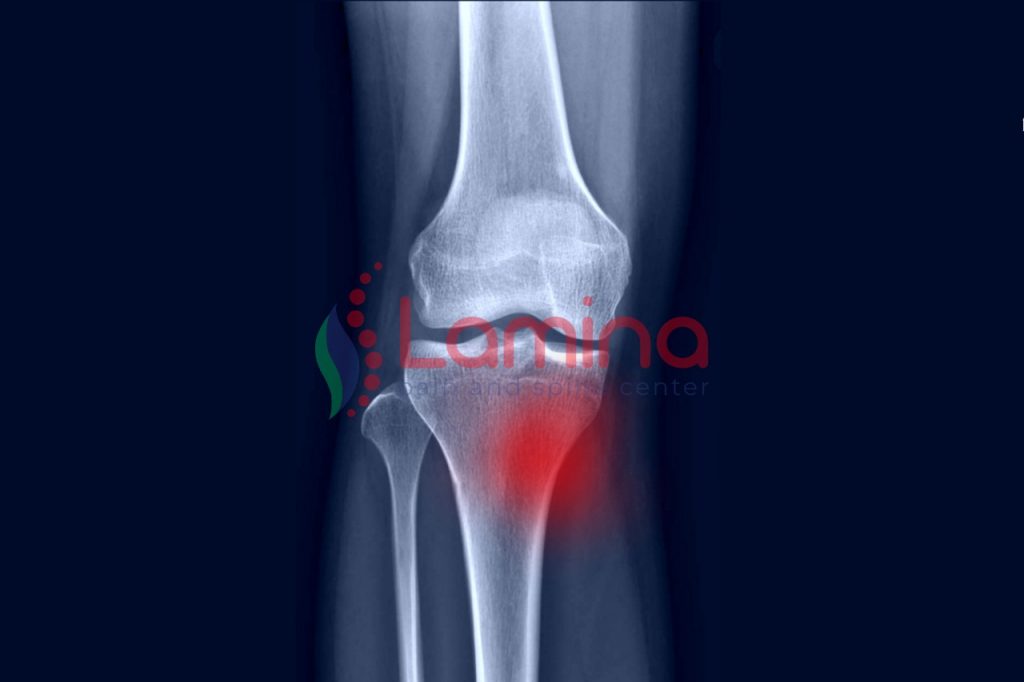

Osteoarthritis

Osteoarthritis (OA) umumnya dikenal dengan pengapuran sendi. OA termasuk jenis radang sendi yang paling sering terjadi dan biasanya menyerang orang-orang berusia lanjut. Pengapuran sendi ini terjadi karena adanya penipisan pada tulang rawan sehingga lebih mudah mengalami kerusakan. OA biasanya juga berkembang secara perlahan seiring bertambahnya usia.